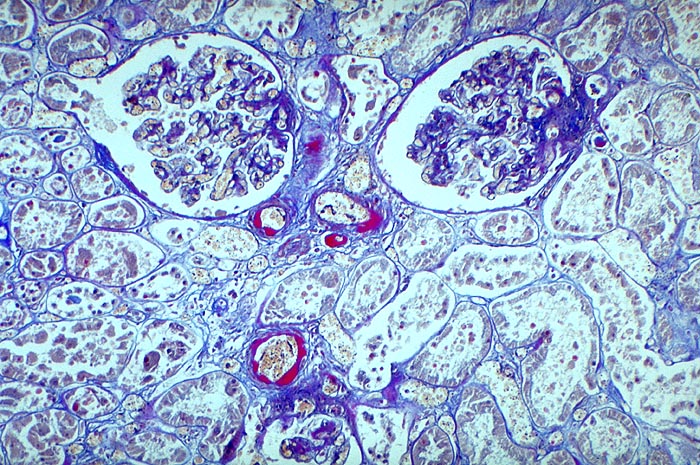

Arteriolosklerose von Vas afferens und Vas efferens bei Diabetes

Plumpe subendotheliale Proteinablagerungen von roter Farbe in den Arteriolen.

Typisch für Diabetes mellitus ist der Befall von Vas afferens und efferens, oft auch der Vasa recta. In intrarenalen Arterien unspezifische Atherosklerose teilweise mit Atheromen (typisch für Diabetes). Der Schweregrad korreliert im allgemeinen mit dem Ausmass der exsudativen Läsionen der Glomerulosklerose. Die Arteriolosklerose im Vas afferens beim Diabetes ist identisch mit der Arteriolosklerose bei arterieller Hypertonie.